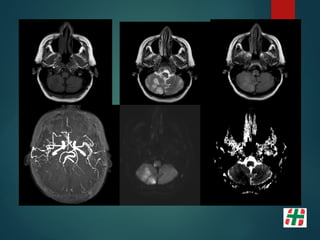

MOYA MOYA

Paciente mujer 56años, fumadora. Episodios repetidos de déficit transitorios en ambos hemicuerpo, mayormente del lado derecho.